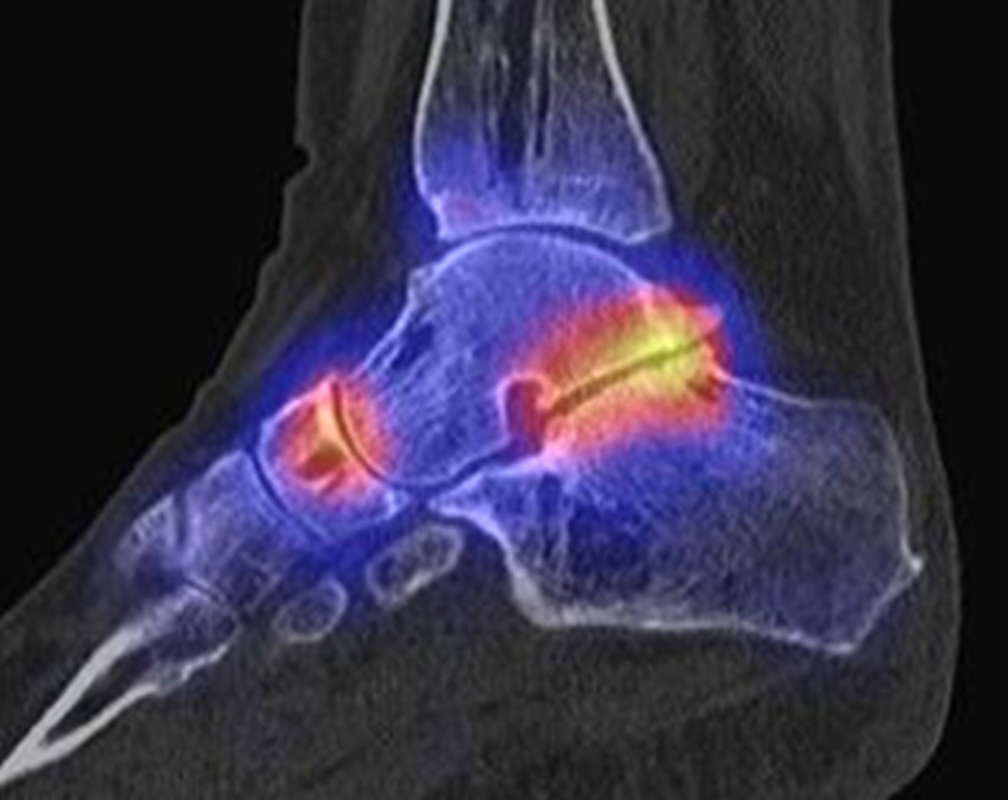

Einen solchen Fall zeigt die Abbildung 3.6., der bei uns untersucht wurde. Bei diesem Patienten bestanden chronisch persistierende Schmerzen seit 3 Jahren infolge einer Distorsion. Zwei vorhergehende MRT-Untersuchungen 1 Jahr und 2 Jahre nach dem Trauma waren nicht wegweisend. Wegen persistierender Beschwerden wurde uns der Patient zum SPECT/CT zugewiesen. Nach operativer Entfernung des Ossikels war der Patient dauerhaft beschwerdefrei.

Zum Lesen der Bildbeschreibung und zur Vollansicht bitte das Bild anklicken. Bild: H. C. Rischke